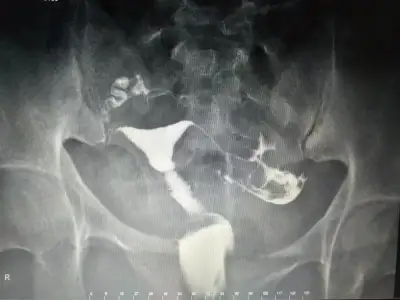

Gerci aranızda en ümitsiz vaka benim heralde 2 aşılama 3 tüp bebek tedavisi denedim 1 dusugum var benimki kendi kendine olucak iş değil ama umut işte 😔

• 20200302_233324.webp

20200302_233324.webp